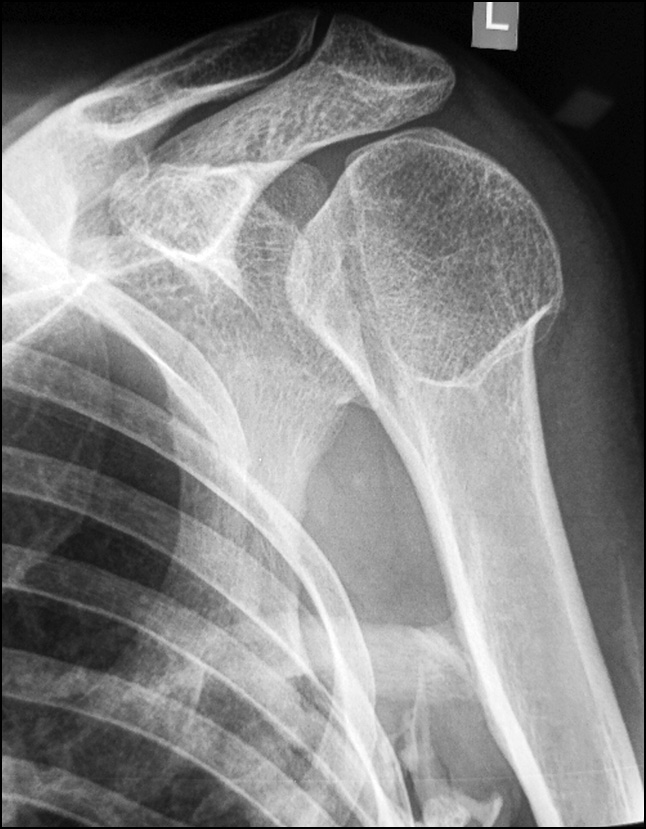

Control radiographs revealed multiple heterotopic ossifications of the axial and peripheral skeleton and submandibular region and multiplanar spinal deformity (Figs. 1–3). Computed tomography revealed synostosis of the 2nd–5th cervical vertebrae, which exhibited fusion of not only their posterior elements but also their bodies (Figs. 4 and 5). Synovial chondromatosis, one of the most common manifestations of FOP, was identified during a hip joint examination (Fig. 6). In addition to intra-articular chondromal bodies, heterotopic ossifications in the hip joints completely inhibit the movements in this skeletal region and significantly impeded walking (Figs. 7 and 8).

Fig. 2. Radiograph of the shoulder joint: heterotopic ossificatum emanating from the humerus and restricting movement in the shoulder joint.